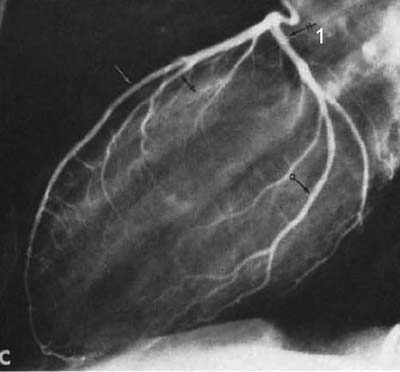

図14 選択的左冠動脈造影,右斜位撮影.上:内膜剥離術前,下:術後. [20]

【要旨】上腕動脈をカットダウンしてカテーテルを挿入し,先端をValsalva洞の冠動脈口に置き,2~5ccの造影剤を注入した.5インチの光電子増倍管の透視像を35mmシネカメラを使って毎秒60フレーム撮影してビューワで動画を観察し,キーフィルムは2×3cmの印画紙に焼きつけた.

1,020例に対して7,207回の造影を行ない,2本の冠動脈にカテーテルを挿入できたのは954例,いずれの冠動脈にもカテーテルを挿入できない例はなかった.合併症としては,12例で心室細動が発生,うち2例が死亡,この他に1例が冠動脈攣縮で死亡し,死亡率は0.29%であった.上腕動脈切開部の閉塞が6~7%に見られたが,多くは無症状であった.

所見としては,動脈硬化症による狭窄,閉塞の描出,機能的狭窄の鑑別,石灰化,冠動静脈瘻などが描出できた.

【解説】冠動脈にカテーテルを挿入して造影する選択的冠動脈の初報である.実際にSonesがこの方法を始めたのは1958年であるが,その後技術を改良し,4年間にわたる症例を蓄積して発表されたものである*.これ以前の冠動脈造影は,いずれも上行大動脈の直接穿刺あるいは末梢から大動脈起始部に挿入したカテーテルからの大動脈造影で,冠動脈に流入する造影剤を利用する方法であった.冠動脈に造影剤を注入しても危険がないことを偶然知ったSonesは,専用のカテーテルを開発してシネフィルムに記録する一連の検査法を確立した.

この論文には写真が掲載されていないが,その後この方法を様々な臨床例に応用した多数の論文に症例が供覧されている(図14). 35mmカメラの記録なので空間分解能には限界があるものの十分診断可能な画質であるが,動脈のカットダウンが必要であり,一般的な臨床検査として普及するには,1967年,Judkins, AmplatzらによるSeldinger法による冠動脈造影の登場を待つ必要があった.